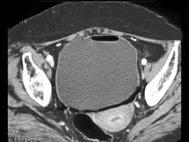

问题 女,54岁,腹胀、肉眼血尿2天,有糖尿病病史,请根据所示图像,选择最可能诊断 ( )

选项 A、膀胱癌 B、膀胱息肉 C、膀胱炎 D、气肿性膀胱炎 E、未见异常

答案 D